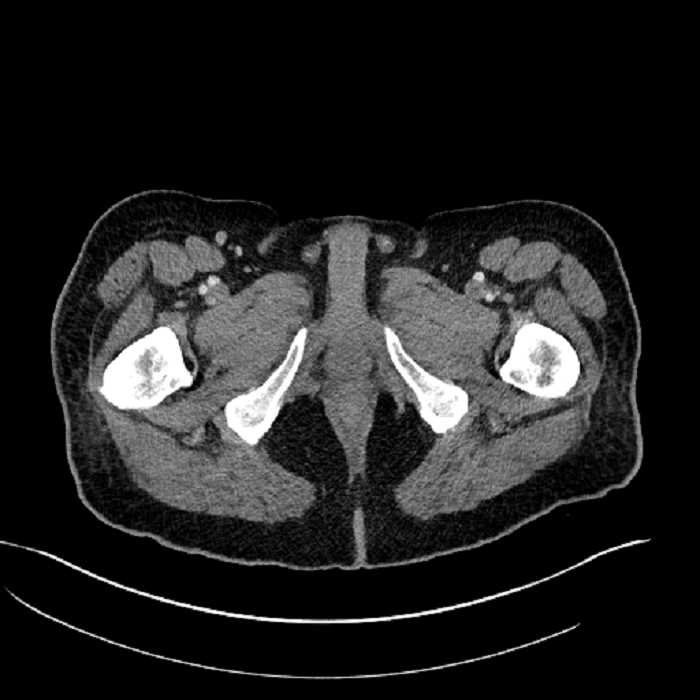

• High grade stenosis of the left common iliac artery, with the left internal and external iliac arteries remaining patent

• Ankylosis of both sacroiliac joints

High grade stenosis of the left common iliac artery. The left external and internal iliac arteries are patent.

Hepatic abscess showing the double target sign with low density internally surrounded by a thin inner enhancing rim (red arrow) and ill-defined outer low density rim (yellow arrow). Blue arrow indicates an internal septation. Red arrows: additional smaller subcapsular abscesses. Red arrow: focal contained perforation associated with diverticulitis.